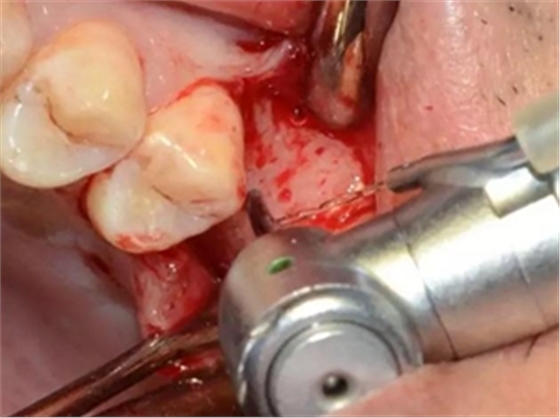

定點(diǎn)定向,初步擴(kuò)孔

使用止停環(huán)控制深度,逐級(jí)預(yù)備打開嵴頂入路。探之竇膜力反饋正常,呈持續(xù)張力。手動(dòng)探查分離通路周圍竇粘膜并略提升。